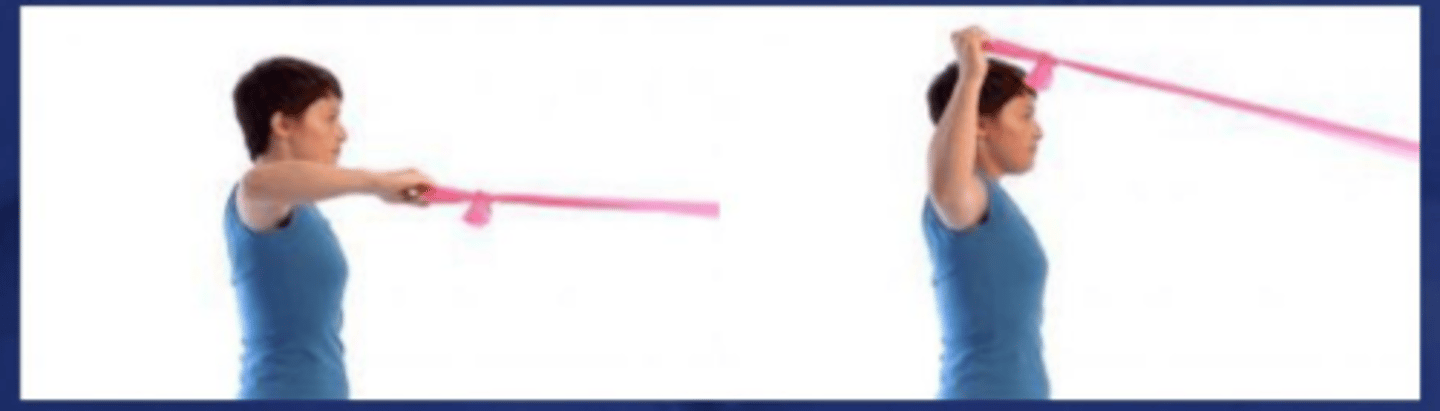

Diagonal pattern flexion

What does the image show?

Diagonal pattern extension

What does the image show?